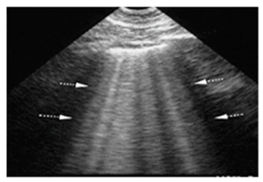

| ARDS | “Multiple non-homogeneous B-lines with a non-gravity-dependent distribution, potentially coexisting with spared areas, along with pleural thickening, reduced or absent lung sliding, and subpleural or trans-lobar consolidations.” | ![]() |